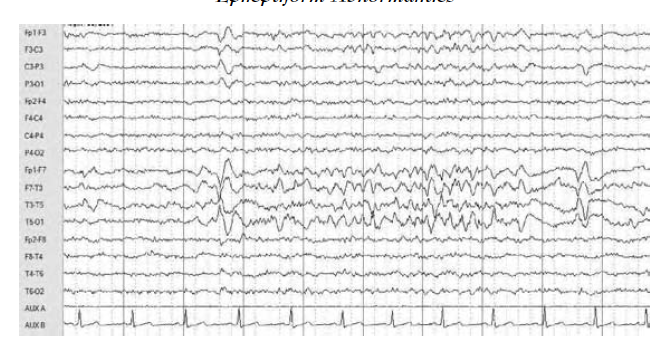

WHAT ED ARE SEEN?

Different morphologies include sharp waves (seen during seconds 1 and 2), spikes and sharp waves (in second 3), polyspike-and-slow waves (in second 4), and spike-and-wave discharges (in the last second of the figure) recorded during an ambulatory EEG in a patient with epilepsy.